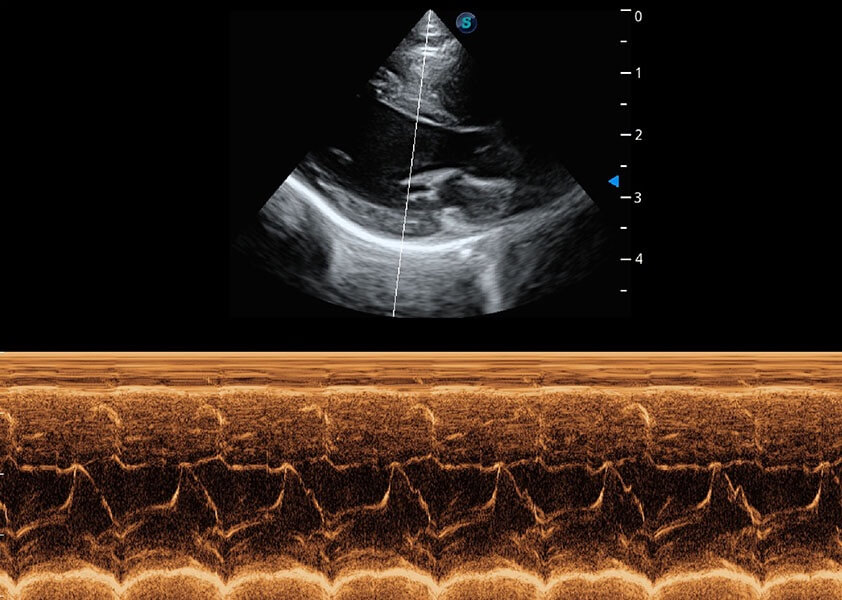

ProPet 60 作为一款高端台式动物超声设备,为动物医生的日常诊断提供了一系列贴合动物临床需求、解决临床实际问题的高级成像功能。凭借全系列高清探头,满足医生对腹部、心脏、生殖、浅表、肌骨等成像的所有需求,切实帮助您提升检查效率,提高诊断信心。

ProPet 60 尊享版

兽用彩色多普勒超声诊断系统